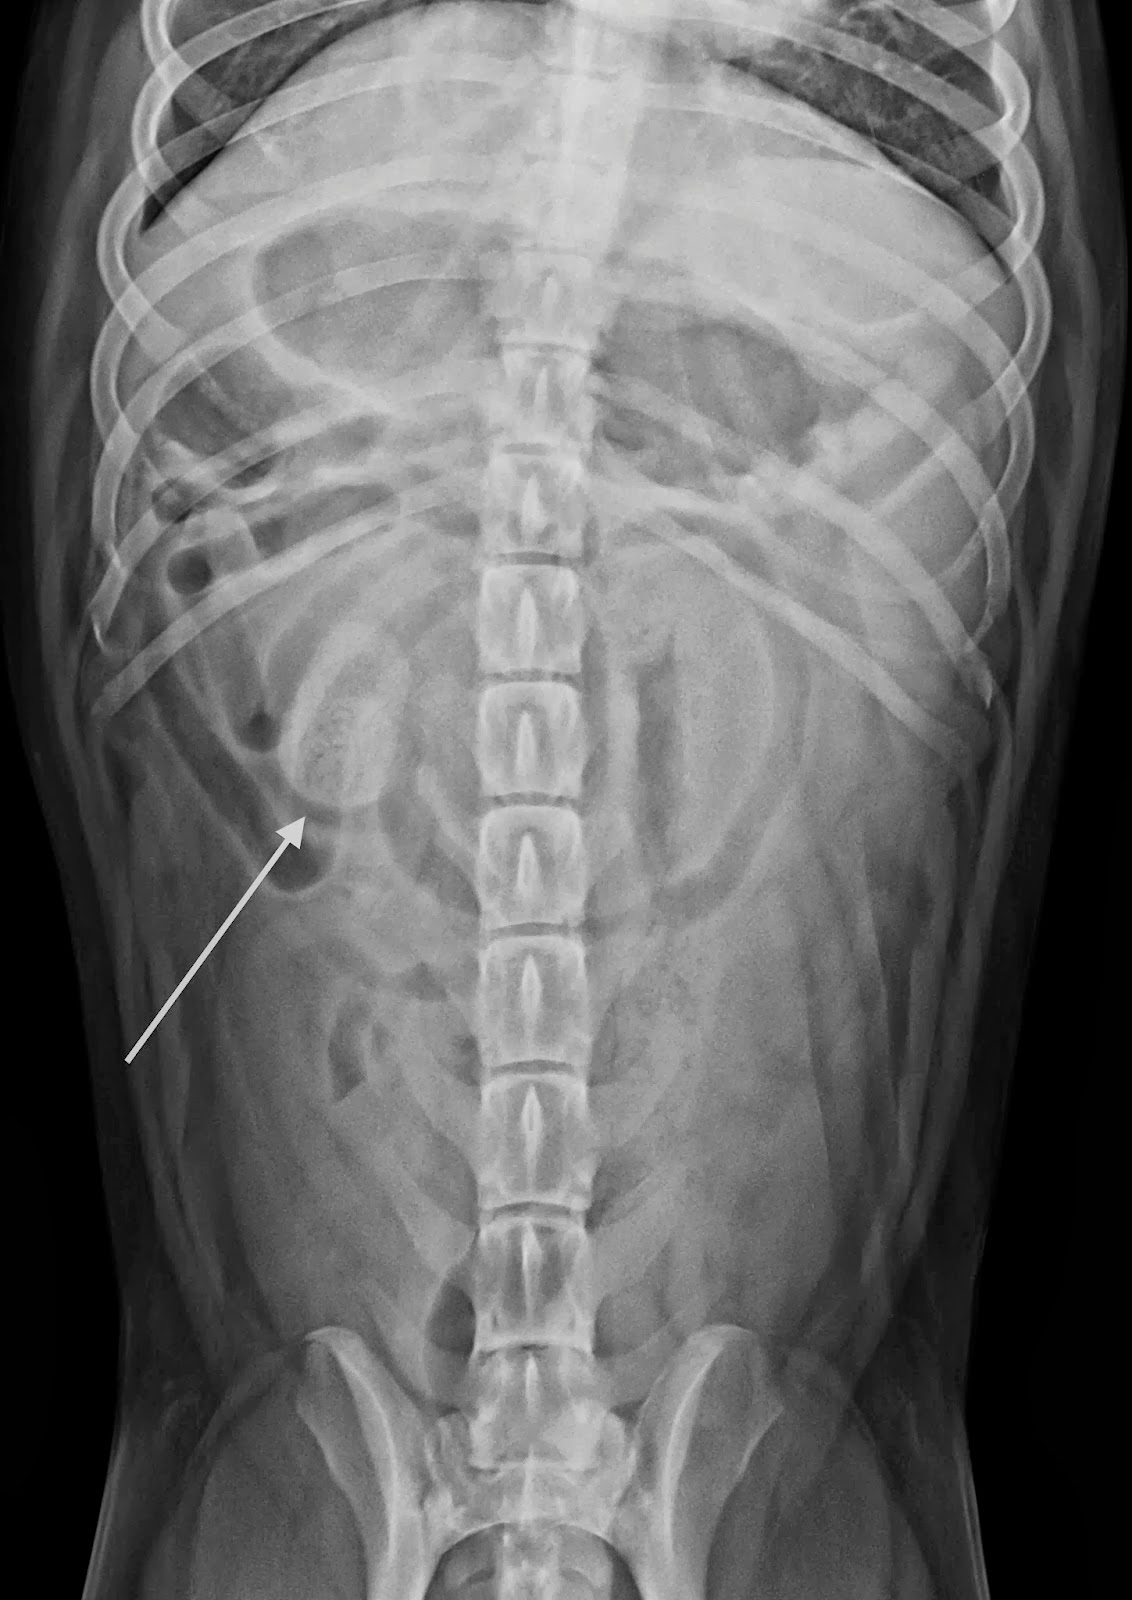

Dog Abdomen X Ray Vd . Learn how to identify normal anatomy and. See examples of normal and abnormal intestinal loops, dilation, and foreign bodies on ventrodorsal views. learn dog osteology with radiographs of normal and pathological conditions. See examples of different views and techniques to improve your diagnostic skills. learn how to interpret ventrodorsal (vd) radiographs of the abdomen in dogs and cats. Figure 1 — a sedated. vd positioning video, 22 of 39 vd positioning video; Position sedated patient in dorsal recumbency (spine to the plate, with legs in the air). learn how to interpret abdominal radiographs for various diseases and conditions in dogs, such as vomiting, foreign bodies, obstruction, and calculi. learn how to use abdominal radiographs to diagnose or rule out mechanical obstruction of the small intestine in dogs and cats. Ventrodorsal diagnostic quality image, 23 of 39 ventrodorsal diagnostic. See examples of normal and.

Dog Abdomen X Ray Vd Position sedated patient in dorsal recumbency (spine to the plate, with legs in the air). learn how to interpret abdominal radiographs for various diseases and conditions in dogs, such as vomiting, foreign bodies, obstruction, and calculi. learn how to use abdominal radiographs to diagnose or rule out mechanical obstruction of the small intestine in dogs and cats. See examples of different views and techniques to improve your diagnostic skills. Ventrodorsal diagnostic quality image, 23 of 39 ventrodorsal diagnostic. Position sedated patient in dorsal recumbency (spine to the plate, with legs in the air). learn how to interpret ventrodorsal (vd) radiographs of the abdomen in dogs and cats. Learn how to identify normal anatomy and. See examples of normal and. See examples of normal and abnormal intestinal loops, dilation, and foreign bodies on ventrodorsal views. learn dog osteology with radiographs of normal and pathological conditions. Figure 1 — a sedated. vd positioning video, 22 of 39 vd positioning video;